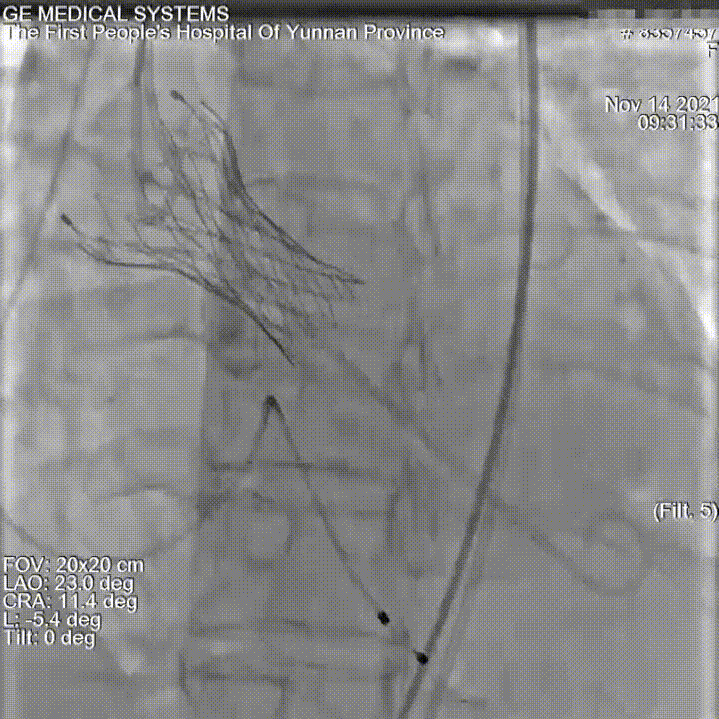

主动脉根部评估:

根部概览

瓣上评估